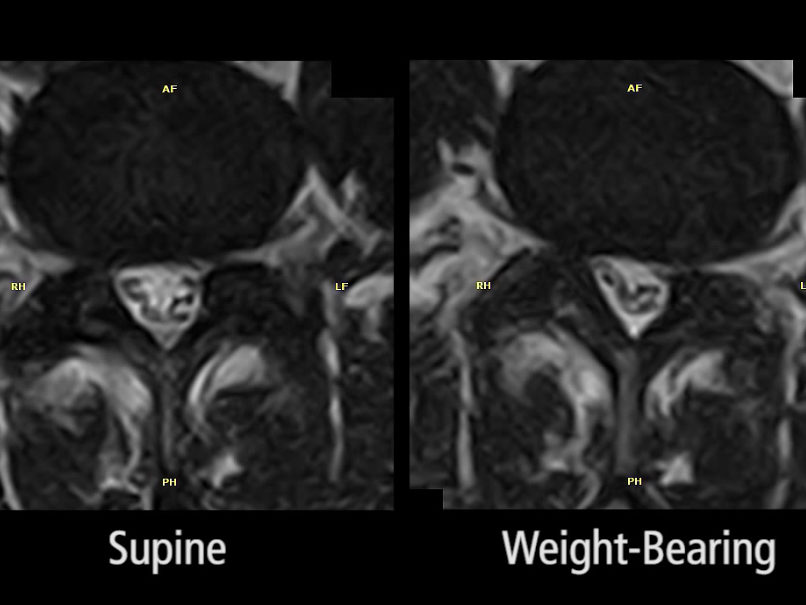

Unique Weight-bearing MRI Capabilities

Weight-bearing studies are easy to perform, allowing patients to be images in the position in which they experience symptoms and providing documentation that can be critical in pre-surgical workflow.